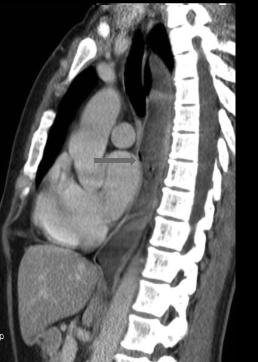

Mega oesophage : image radiologique

TDM fenetre parenchymateuse en coupe axiale |

Image Achalasia de oesophage en

coupe TDM sagitale |

Meme cas en coupe TDM frontale ( coronale

) . |